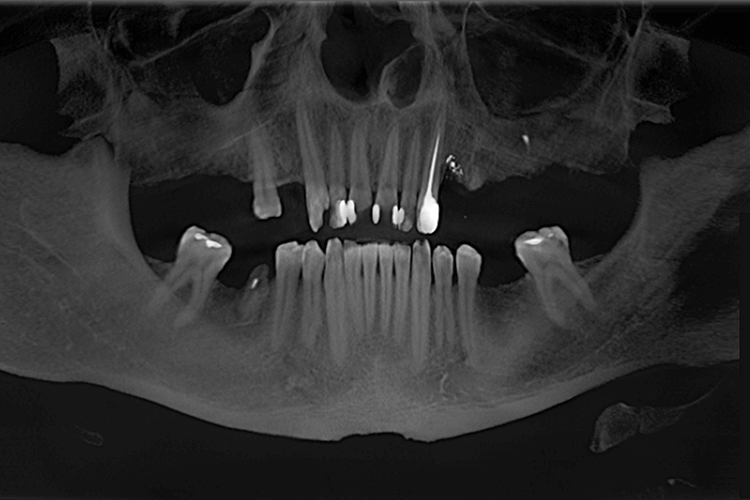

Во время проведения диагностики был обнаружен глубокий кариес фронтальных зубов, незначительная стертость фронтальных нижних зубов в связи с нарушением прикуса, а также отсутствовали нижние 6-е зубы с обеих сторон.

Корни зубов, которые ранее служили опорой для мостов на верхней челюсти, были разрушены и подлежали удалению, также в области этих зубов обнаружили кистогранулемы.